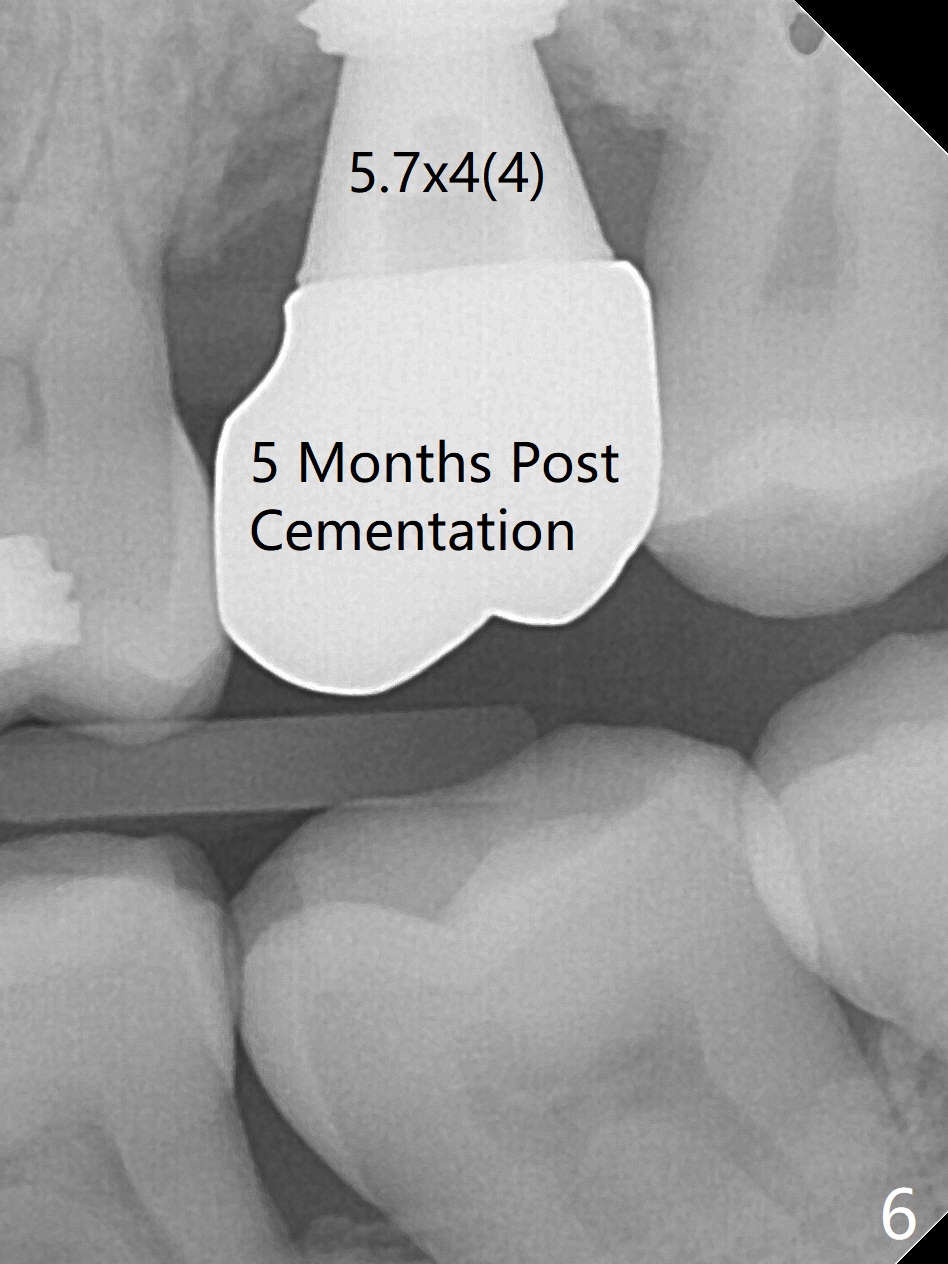

The implant plateau remains to be covered by the bone 5 months post cementation (Fig.6,7 *).